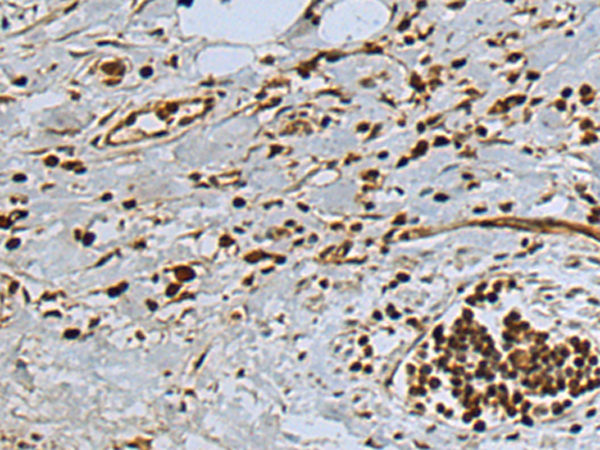

IHC positive control: |

Human gastric cancer |

IHC Recommend dilution: |

100-300 |